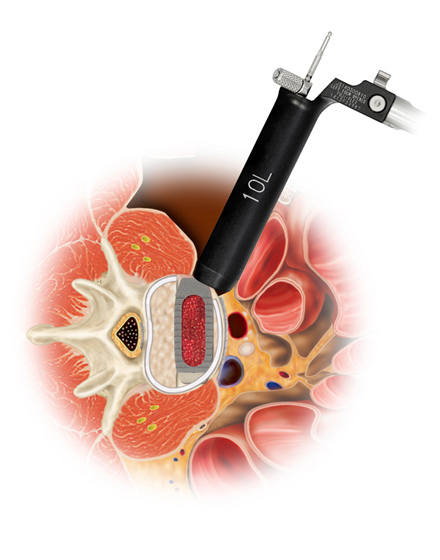

低侵襲脊椎側方固定術 XLIF (エックスリフ)、OLIF(オーリフ)

日本では2013年から承認されている低侵襲な脊椎側方固定術です。この手術は、トレーニングを受けた医師だけが実施できるため、全国でも限られた医療機関でのみ受けられます。当センターの日方医師は資格を有しているため実施可能です。この手術の最大の利点は脊髄神経を直接触らないで神経を圧迫から解除することにあります。側腹部に約5cmの皮膚切開により、下図のように神経機能を電気モニタリングで随時確認し重要な神経を避けながら椎間板内に人工骨を移植します。その後、腰部から固定術を行います。翌日から起立・歩行が許可され、入院期間は通常10~14日程度になります。